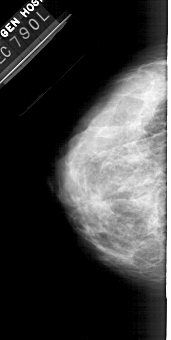

A_1364_1.LEFT_MLO

LEFT_MLO LINES 5491 PIXELS_PER_LINE 2686 BITS_PER_PIXEL 12 RESOLUTION 43.5 NON_OVERLAY